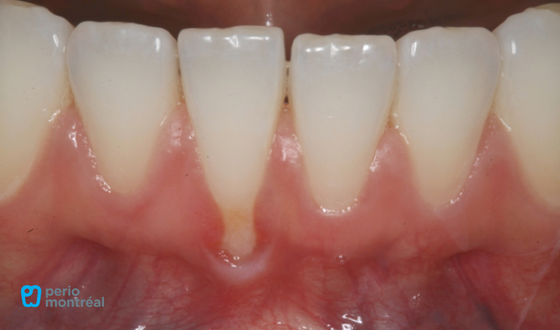

This patient “L.P.” presented with a chief complaint of “I bit in to a peach and caused this recession”. There is a Miller Class II recession defect on tooth #41 with a lack of keratinized tissue. The patient reports mild sensitivity to brushing.

- Miller Class II recession tooth #41

- Lack of keratinized tissue #41